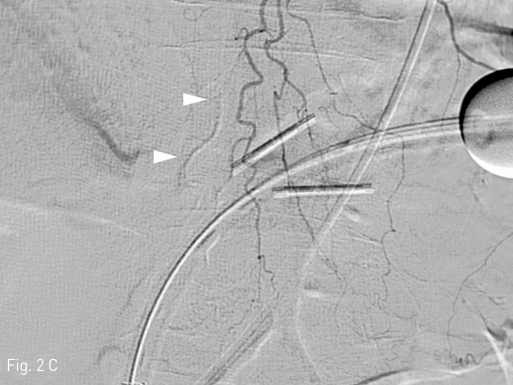

Fig 2C

On follow-up arteriography, artifact by the NBCA-ethiodized oil mixture is noted (C, arrowheads), and there was no evidence of further active arterial bleeding.